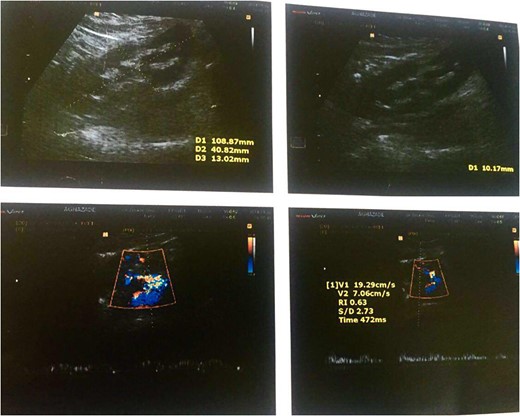

Color Doppler ultrasound of the transplanted kidney 2 months after surgery.

Color Doppler ultrasound of the transplanted kidney 2 months after surgery in the zoomed area of the image.

Gray-scale ultrasonography of the patient's transplanted kidney 8 months after surgery.